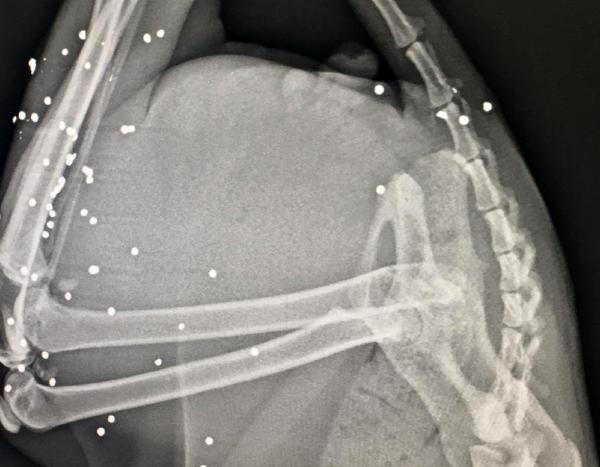

Veteriner Atila Sargın tarafından filmleri çekilen kedinin arka ayaklarının olduğu bölgede çok sayıda saçma izine rastlandı. Yürümekte zorlanan ve arka ayaklarının üzerine güçlükle basan kedinin tedavisine başlanırken, Manavgat İlçe Jandarma Komutanlığı’nca olayla ilgili inceleme başlatıldı.

Veteriner hekim Atila Sargın da Şenay Yılmaz'ın kendisini aramasından sonra olaydan haberdar olduğunu belirterek, “Gelip baktığımda kedinin durumunun kötü olduğunu gördüm. Hemen aldım kliniğe götürdüm. Röntgeni çekince gördüm ki kedinin arka tarafında çok sayıda saçma var. Yani kedinin arka tarafında tüfekle ateş edilmiş. Bu kedi teyzenin canı gibi. Bir yıldır tanıyorum teyzeyi. Sürekli gelip kediye bakardım, onun aşılarını filan yaptım. Şu an kedinin tedavisine devam ediyoruz” diye konuştu.

'80 TANE SAÇMA VAR'

Hayvanlara yönelik şiddete son verilmesi gerektiğini belirten Sargın, sözlerini şöyle sürdürdü: “Bu canlarımıza artık böyle insanlar silah sıkmazsa, kurşun sıkmazsa çok mutlu olacağız. Kedinin vücudunda çok miktarda saçma var, belki 70- 80 tane. Bunu tek tek ameliyatla toplama şansımız yok. Bunu kedi enfeksiyon kapmadan bir şekilde düzelteceğiz. Zaten 2 gün öncesine göre şu an biraz daha iyi."

Deri altında olan saçmaların operasyonla alınacağı, derinde olanların ise alınması durumunda hayvanın daha fazla zarar göreceği için çıkarılmayacağı ve ilaç tedavisiyle zarar vermeyecek hale getirileceği öğrenildi.